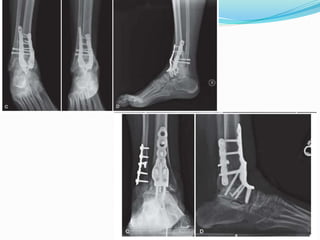

ANTERIOR APPROACH WITH

PLATE FIXATION

 This approach is particularly appropriate for

conversion of a failed total ankle arthroplasty to

arthrodesis

 Plaass et al. described an anterior double-plating

technique for severe osteoarthritis, nonunion of ankle

arthrodeses, and failed total ankle replacements

 They suggested that the stiffer two-plate system may

improve clinical fusion rates, especially in patients

with suboptimal bone quality.